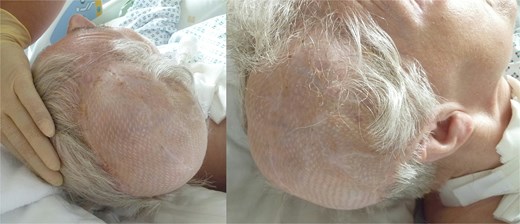

Complication: scalp necrosis

Shortly after transfer to the neurorehabilitation center, the patient developed scalp necrosis over the site of the reimplanted bone flap (Fig. 4a). This complication was likely attributable to impaired vascular healing, potentially related to the earlier injury of the superior sagittalis sinus. The patient was subsequently transferred back to the hospital for surgical debridement.

(a) Necrosis of the scalp in the area of the previously performed cranioplasty, (b) explanted necrosis area.